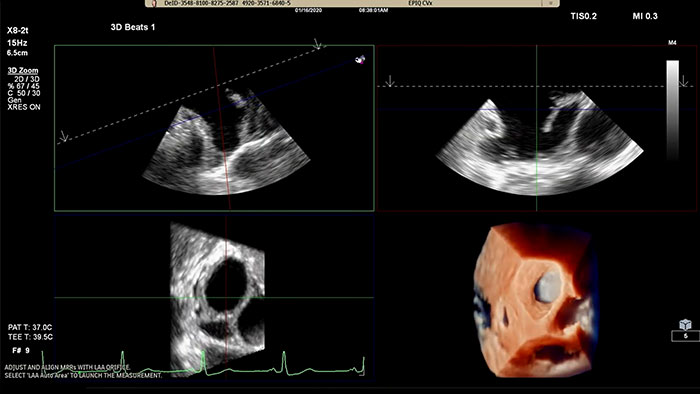

Быстрое измерение отверстия в ушке левого предсердия с использованием традиционных алгоритмов визуализации или алгоритмов визуализации TrueVue Glass с приложением 3D Auto LAA